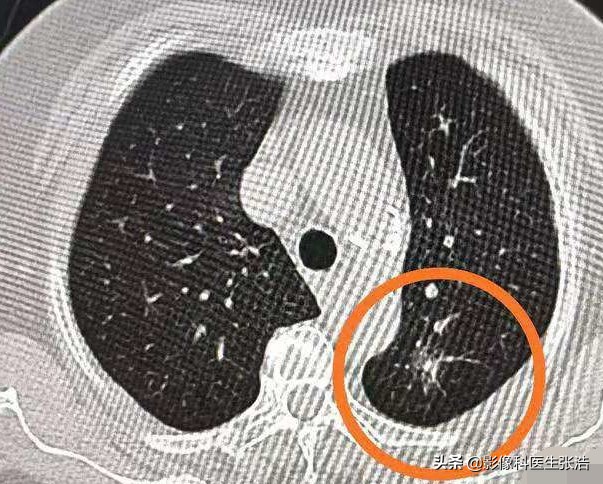

首先明白一点,并不是发现了磨玻璃结节就一定是肺癌的。下图就是一个典型磨玻璃结节,但是结果并不是恶性的,一月抗炎复查完全消失,诊断是一个炎性结节。